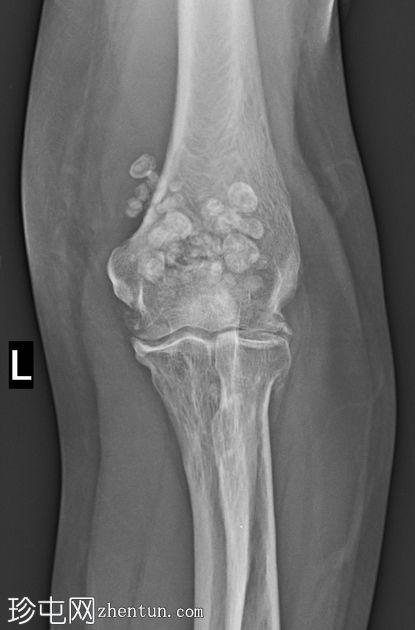

1.jpeg

正面

肘关节内多个边界清晰的钙化/骨化游离体,主要位于前后凹处。关节面不规则、骨赘形成、关节间隙狭窄以及肱骨远端、尺骨近端和桡骨头的软骨下硬化均符合骨关节炎的改变。桡骨头轮廓不规则,并有一条模糊的硬化线,提示为陈旧性愈合骨折。无急性骨折或脱位。